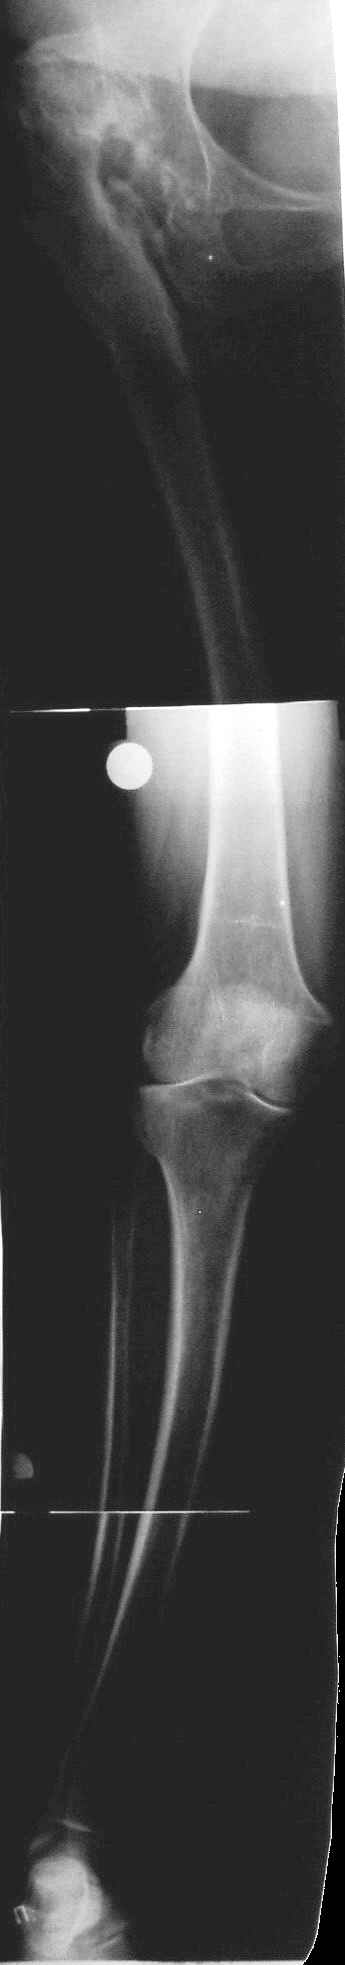

Уважаемые коллеги! Хотелось бы услышать Ваше мнение относительно тактики лечения данной пациентки. Пациентка 1953 г.р. поступила в клинику с диагнозом: "Деформирующий артроз в неоартрозе III ст. между головкой правого бедра и правой подвздошной костью, исход открытого вправления врождённого вывиха правого бедра. АВНГБ слева III-IV ст., коксартроз слева IIIст.Остеобластокластома левой седалищной кости."Из анамнеза: в возрасте 14 лет - открытое вправление врождённого вывиха правого бедра. В 1980 г. остеотомия, дистракционный остеосинтез правой бедренной кости.Зимой 2003г. обнаружена ОБК левой седалищной кости, получила курс лучевой терапии. В настоящее время данных за прогрессирование патологического очага нет. Пациентка поступила для эндопротезирования правого тазобедренного сустава. Учитывая наличие вальгусной деформации правого бедра и костей правой голени, возник вопрос, что выполнять в первую очередь - эндопротезирование, или же корригирующие остеотомии с исправлением оси конечности? Мнения коллег разделились.Заранее благодарны за помощь.

С отведением у пациентки проблемы - 0 град., приведение до 30 град, сгибание/разгибание=140/150 град., внутр. ротация 0 град., наружная ротация 20 град. Относительное и ортопедическое укорочение правой нижней конечности всего 1 см.(в 1980г. удлинение правого бедра на 4 см.). Имеются признаки остеохондроза дисков поясничного отдела позвоночника.

Учитывая отсутствие выраженной фиксированной приводящей контрактуры, рассматривали вариант первичной коррекции вальгусной деформации конечности.

Второй рассматриваемый вариант - эндопротезирование правого тазобедренного сустава с низведением и коррекцией деформации на уровне проксимального отдела бедра. Вторым этапом - коррекция вальгусной деформаци голени.